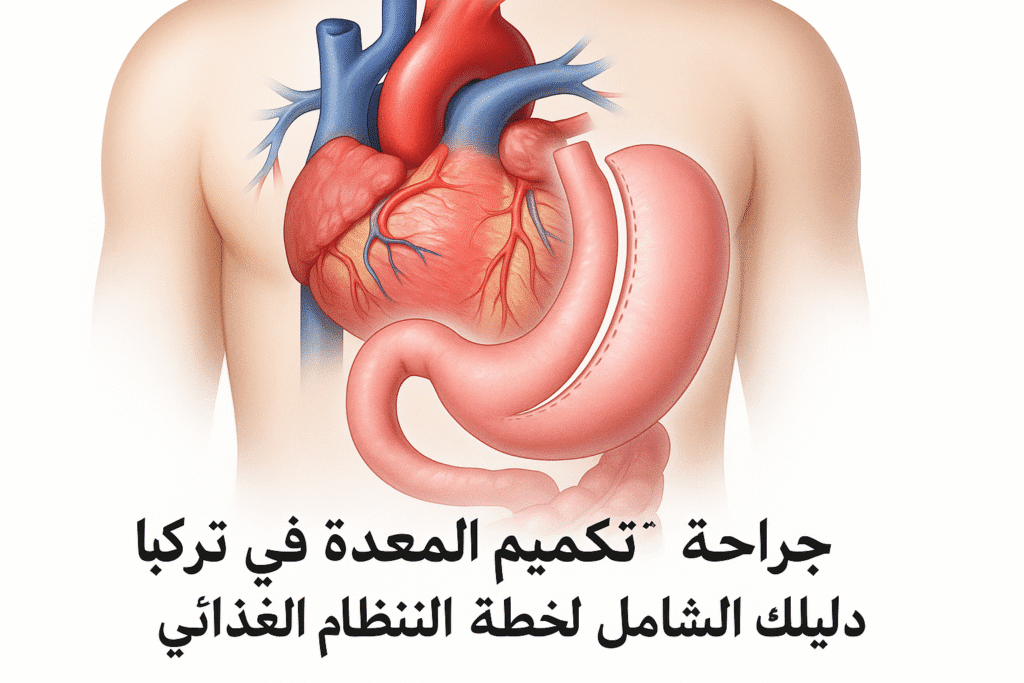

مقالات طبية من مساهمات الأطباء